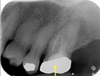

what would you expect to see on a radiograph of normal periapical tissues?

• radiolucent (black) line of PDL space

- even width around the tooth

• radiopaque (white) lines that represents lamina dura

• continuous around the root